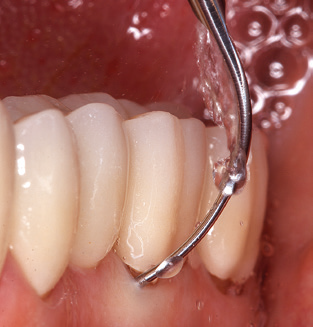

Of course, working tips for the cleaning of implant surfaces are also indispensable for SPT in patients fitted with implants. The implant cleaning attachment on the system used here is characterised by its tapered, hexagonal design. This design allows light, atraumatic penetration of the peri-implant pocket and displays a good cleaning performance (Fig. 7).

Fig. 4: Flexible probes with millimetre markings are recommended for the probing of dental implants (e.g. Colorvue Kit PCV11KIT6, Hu­Friedy). – Fig. 5a and b: A straight working tip (1P, W&H Dentalwerk Bürmoos GmbH) is a suitable instrument for use on all natural teeth. – Fig. 6: Curved working tips (3Pr/3Pl, W&H Dentalwerk Bürmoos GmbH) lend themselves to the processing of difficult-to-reach areas of the tooth and root surfaces (e.g. furcations). – Fig. 7: The tapered, hexagonal implant cleaning tip (1I, W&H Dentalwerk Bürmoos GmbH) permits atraumatic and efficient cleaning of the crown and abutment surfaces. – Fig. 8: Titanium and carbon curettes are suitable instruments for the manual cleaning of the implant surfaces.